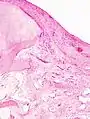

Diagnosis is made with reasonable certainty based on history and clinical examination.[51][52] X-rays may confirm the diagnosis. The typical changes seen on X-ray include: joint space narrowing, subchondral sclerosis (increased bone formation around the joint), subchondral cyst formation, and osteophytes.[53] Plain films may not correlate with the findings on physical examination or with the degree of pain.[54]

X-ray of erosive osteoarthritis of the fingers, also zooming in on two joints with the typical "gull-wing" appearance

Both primary generalized nodal osteoarthritis and erosive osteoarthritis (EOA, also called inflammatory osteoarthritis) are sub-sets of primary osteoarthritis. EOA is a much less common, and more aggressive inflammatory form of osteoarthritis which often affects the distal interphalangeal joints of the hand and has characteristic articular erosive changes on X-ray.[59]